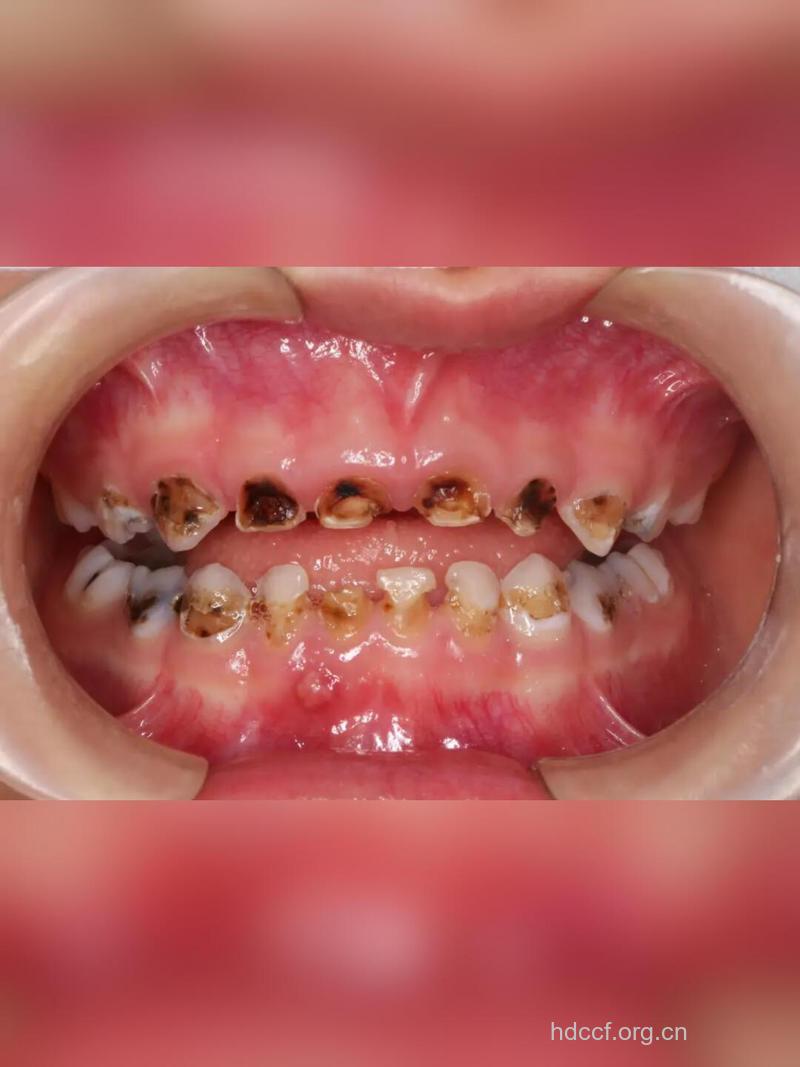

婴幼儿喂养龋是严重危害乳牙列的严重破坏性疾病,这一疾病又是如何发生的呢?最近,北京大学口腔医学院专项调查发现,儿童喂养方式、饮食习惯和口腔卫生习惯与“喂养龋”密切相关。

乳牙龋齿已经成为影响我国儿童健康的主要疾病之一,第二次全国口腔流行病学调查表明,5岁儿童的患龋率为76.55%。随着生活水平的提高,乳牙的患龋率还有逐年上升趋势。

结果显示40.19%,其中男孩为45.07%,女孩为34.87%。研究发现,婴儿睡觉前使用奶瓶易患喂养龋(因奶瓶内多为奶加糖或纯奶),喂养龋患病率随年龄增加而增加;母亲受教育的程度越低,母乳喂养时间越长,孩子刷牙次数越少,喂养龋越高;每天饮用含糖饮料的次数多和刷牙的次数少等均会导致喂养龋发生。这些危险因素可以从一个或多个方面不同程度地导致喂养龋的发生和发展。